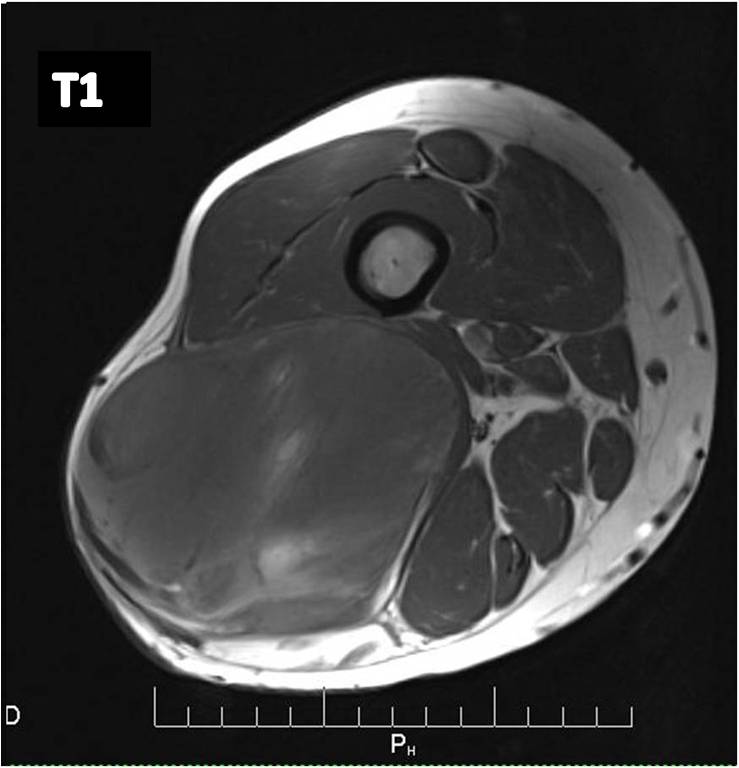

MRI (Fig. 2 and 3)

• Large well defined multilobulated mass.

• Low signal on T1 weighted images. Usually adipose tissue composes less than 10 percent of the tumor and is difficult to detect on an MRI as high signal on T1W images. (Fig. 2A)

• Identification of the subtle fat requires comparison of T1W and T2W images in the same plane but is usually very difficult to discern. (Fig. 2)

Fig 2. T1-weighted MR image (A) of a myxoid liposarcoma demonstrates well-defined mass of intermediate signal intensity with central areas of high intensity. T2 –weighted fat-suppressed image (B) heterogeneously mostly high signal intensity within the lesion.